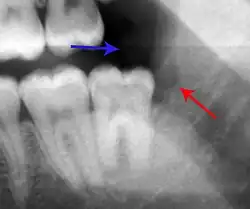

- Radiographs utilized to find dental caries and bone loss laterally or at the apex.

Decay (green) with apical abscess (blue) -

Gutta-percha point indicating abscess origin